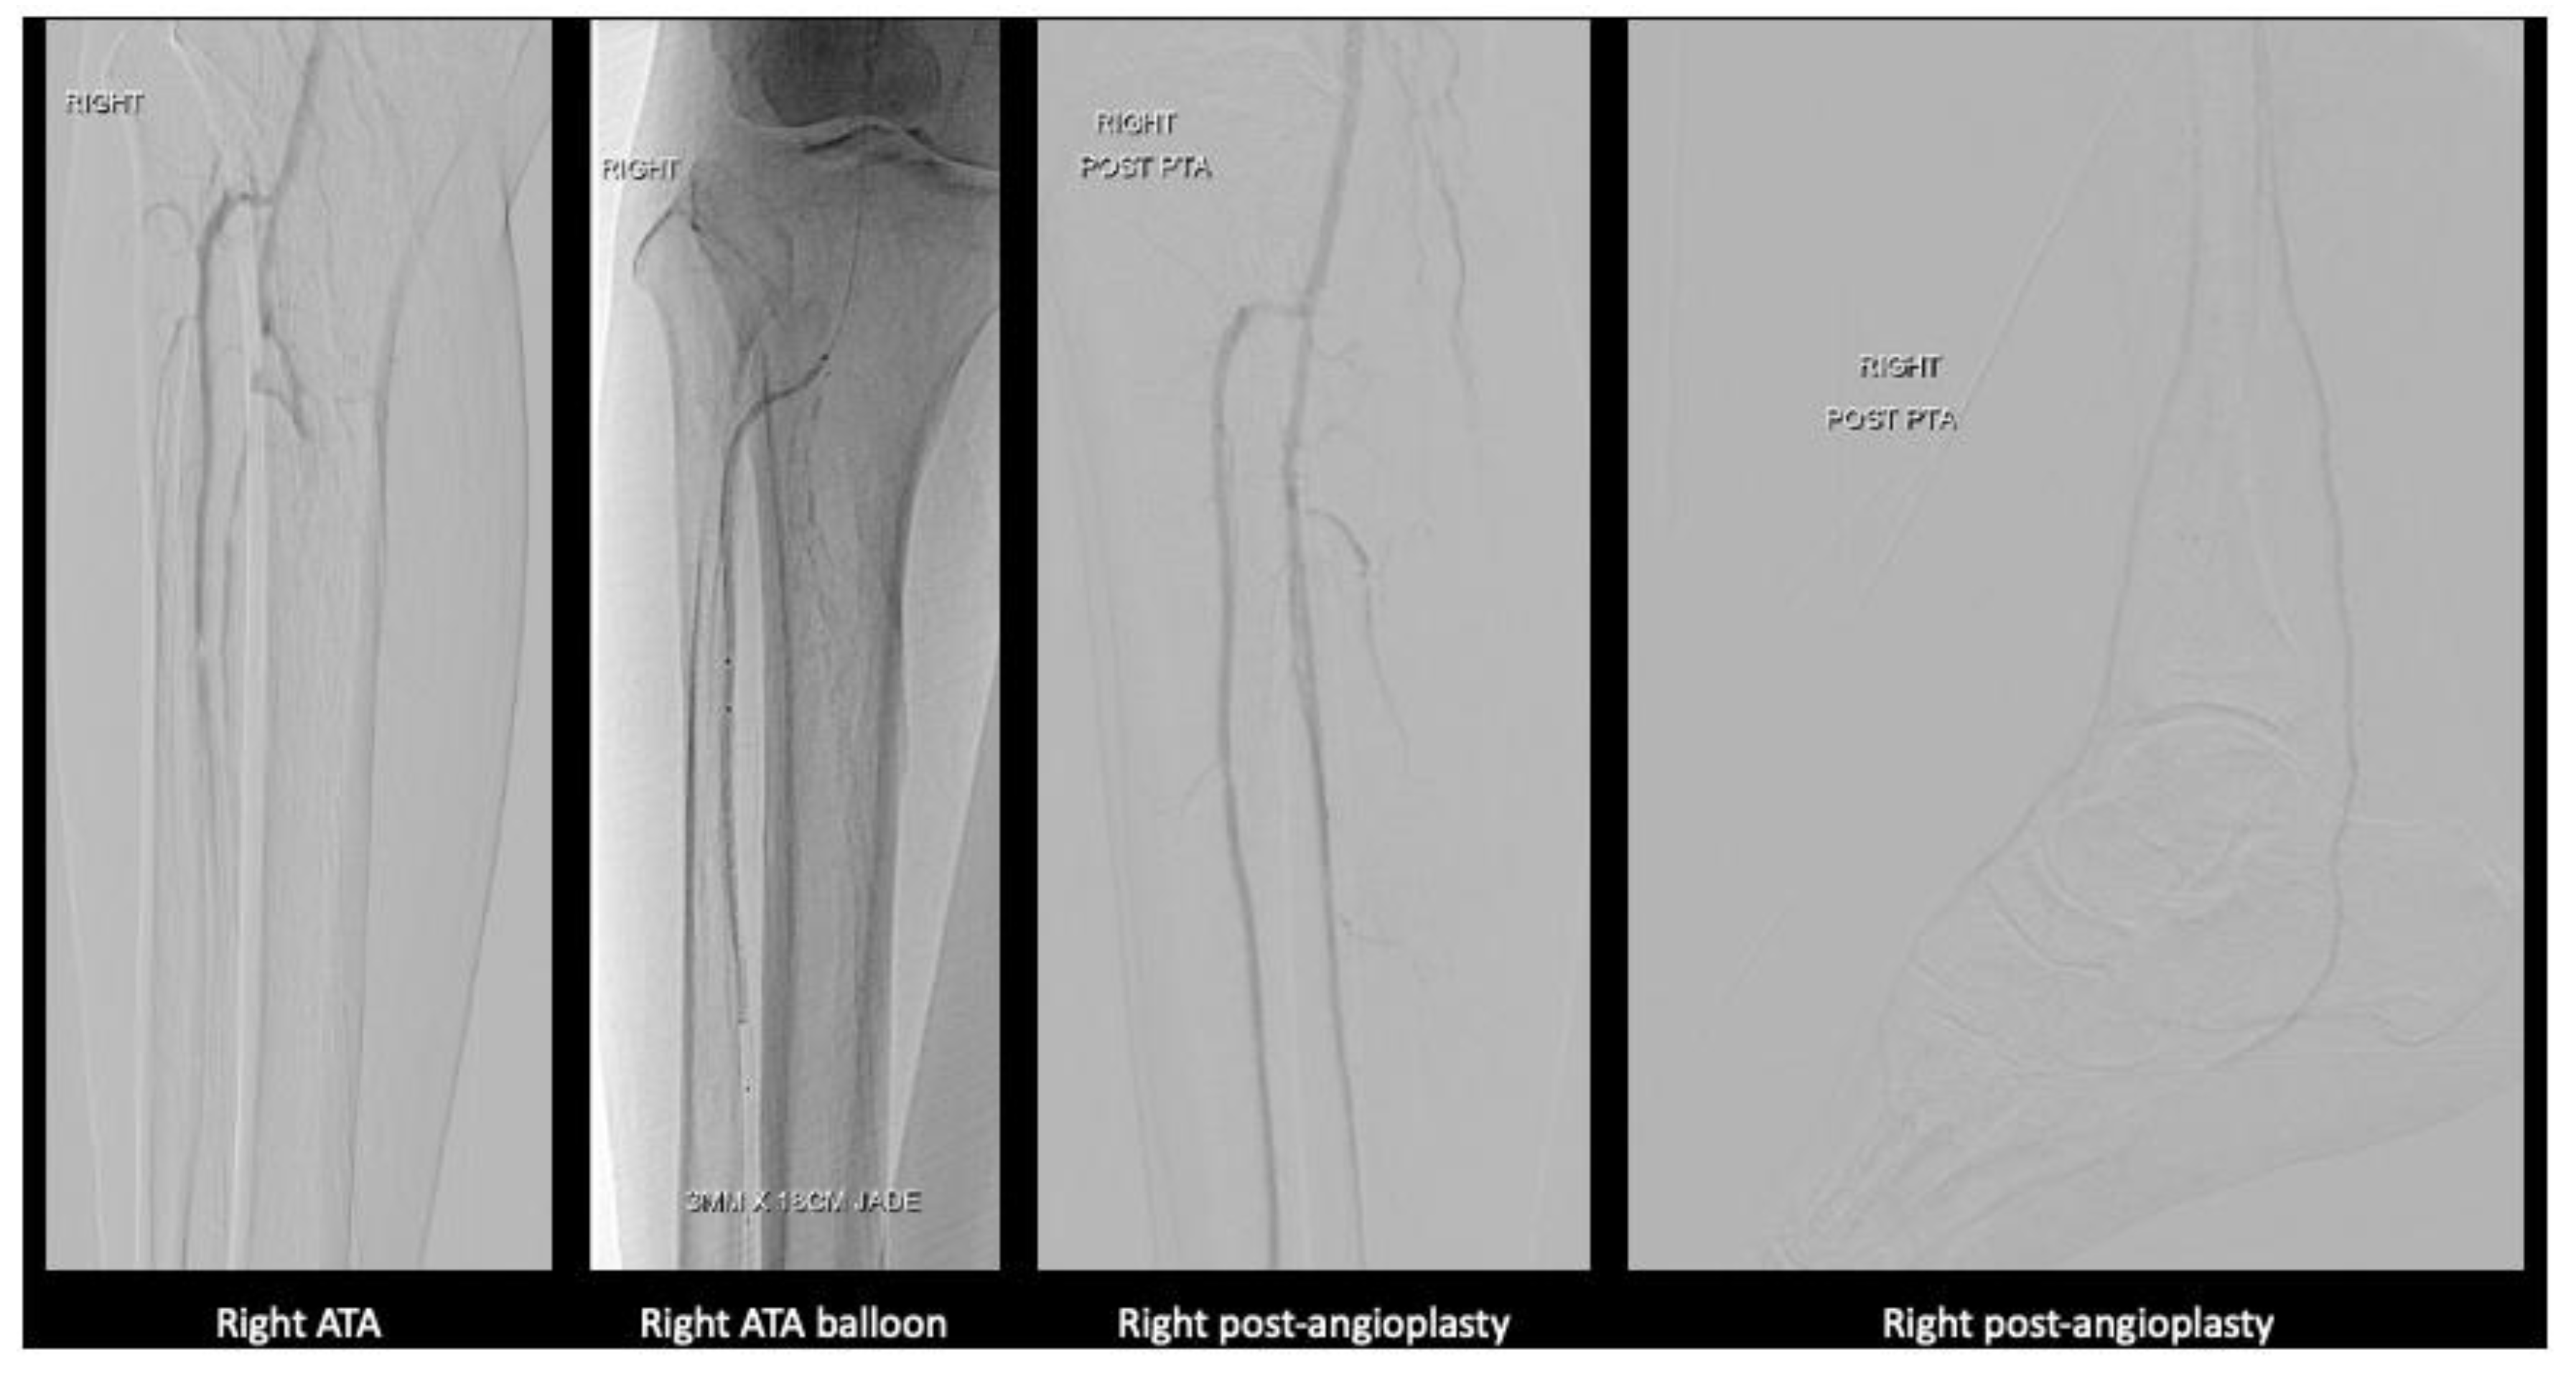

Figure 4. Angioplasty images of the right lower limb.

After much discussion, patient and vascular team decided to attempt limb salvage with bilateral lower limb angioplasties and fifth toe ray amputations at the same setting. Angioplasty to anterior tibial artery, posterior tibial artery, dorsalis pedis, common plantar artery was performed on the right lower limb with successful outcome. On the left lower limb, angioplasty to the anterior and posterior tibial artery was performed. Patient’s wound recovered with combination of culture directed antibiotics, vacuum dressing and motivation from a supportive family.